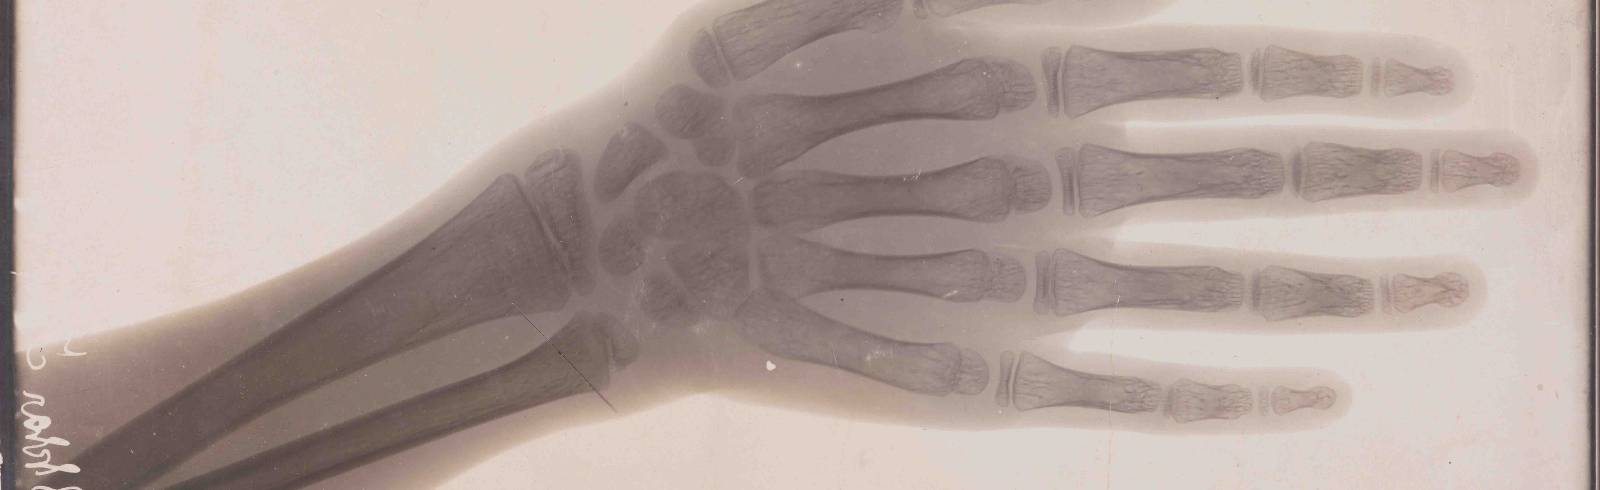

Selbst geschädigt hat sich auch Guido Holzknecht. Der Arzt, Jahrgang 1872, führte die Röntgenologie in Wien ein und erfand ein Röntgendosiergerät. Er schädigte seine Hand in Selbstversuchen dauerhaft, worauf sie Stück für Stück amputiert werden musste. Der Rest von Holzknechts rechter Hand ist ausnahmsweise Teil der Ausstellung, weil er sein Einverständnis gab. Üblicherweise wird auf Anonymität Wert gelegt, wird in der Ausstellung auch auf die ethischen Probleme bei der Nutzung von Körperteilen als Museumsstücke hingewiesen. Patienten um Zustimmung zu fragen, war laut Winter lange nicht üblich.

Ein weiteres Einsatzgebiet von Röntgengeräten waren Schuhgeschäfte. Die Idee kam in den 1920er-Jahren aus den USA und sollte helfen, exakt sitzende Schuhe an Kinderfüße anzupassen. Erst nach 1950 gab es erste Warnungen vor den Röntgengeräten, deren Strahlung Kunden und Personal unkontrolliert traf. Die sogenannten Pedoskope waren noch 20 Jahre später im Einsatz. Inzwischen sind Röntgenstrahlen, entdeckt von Wilhelm Conrad Röntgen, ein wichtiges, nicht-invasives Instrument zur Abbildung von Knochen und inneren Organen.